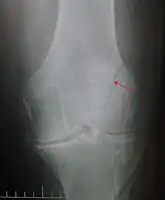

The patella can break in various ways depending on the way it is injured, and into two or more pieces.[1] Types include transverse, with one fracture line and is the most common type,[5] marginal, osteochondral and the rare vertical type, or stellate, where a direct compression force gives rise to a comminuted pattern.[5][7] Patella fractures can be further classified as displaced, where the broken ends of bone do not line up correctly and separate by more than 2mm, or undisplaced and stable where pieces of bone remain in contact with each other.[1][7] If fragments of patella bone stick out from the skin it is known as an open patella fracture, and closed if the overlying skin is intact.[1]

Differential diagnosis

Some people have a normal two-part patella which can appear as a fracture. The fragment is usually seen in the top outer corner of the patella and can be distinguished from a fracture by being present in both knees.[6]